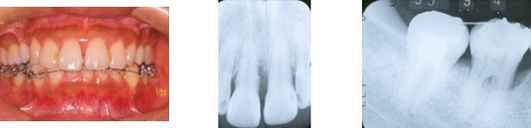

歯周再生治療、エムドゲインを使用した症例

歯周再生治療、エムドゲインを使用した症例です。一本一本の歯、口腔内全体をチェックして治療を行います。